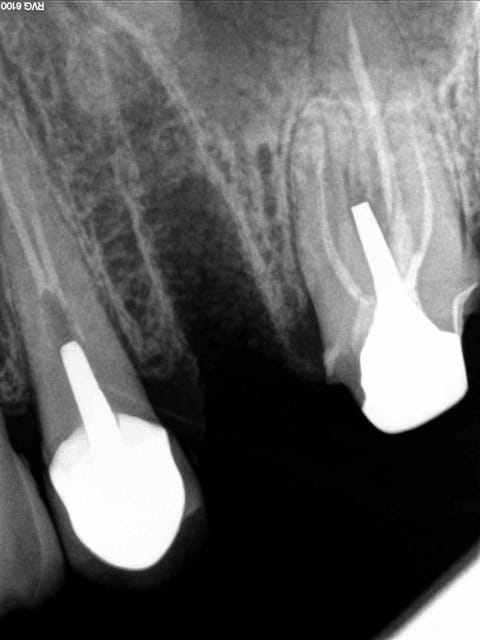

Un confrère : " avec la CCAM, comment il faut coter la radio après pose des faux moignons" ? (10 déc 2014!)

Ben oui, faut savoir que ça existe !!!